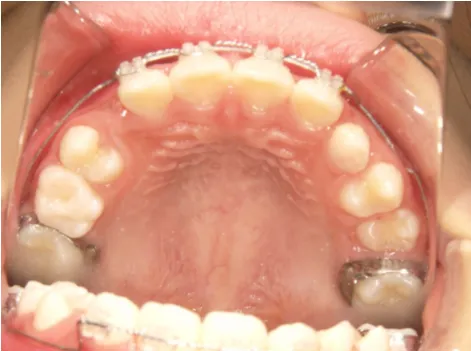

治療スタート:8y2m QH・BHで拡大、前歯の並び替えスタート

QH

BH

ブラケット